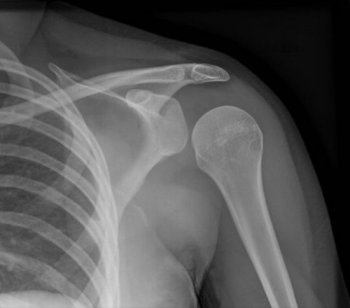

| Вывих плеча | Сильная боль в плече, деформация плечевого сустава, ограничение подвижности, отек, синяки. | Иммобилизация руки с помощью повязки, обезболивание (нестероидные противовоспалительные препараты), срочная медицинская помощь. |

- плечевые суставы,

При постановке диагноза вывиха всегда указывается сегмент, находящийся ниже поврежденной области. Например, если произошел вывих плечевого сустава, диагноз будет звучать как «вывих плеча». Исключение составляют случаи с позвоночником: при его травме диагноз формулируется на основе вышерасположенного позвонка.

При диагностике вывиха важно измерить пульс и оценить чувствительность тканей, чтобы выявить возможные повреждения сосудисто-нервного пучка. Перед вправлением обязательно выполняется рентгенография в двух проекциях. Это позволяет определить характер и степень вывиха, а также наличие сопутствующих переломов, трещин или сколов костной ткани.